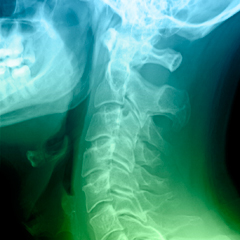

Thecause of the urinary dysfunction is usually multifactorial. Although urinary

dysfunction may entirely be non-neurogenic, it may also present with an overt

or occult neurogenic abnormality underneath. Many clinically relevant methods

have been put forward to allow an early diagnosis and identification of urinary

dysfunction. A detailed patient's history, physical examination, and the

determination of underlying pathophysiology are considered essential components

of the initial evaluation of urinary dysfunction.